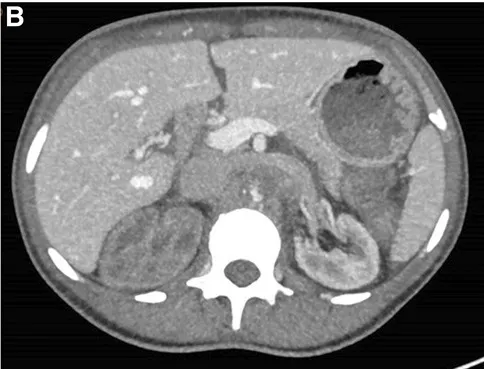

Paciente con dolor lumbar evolucionando con IRA y anuria.